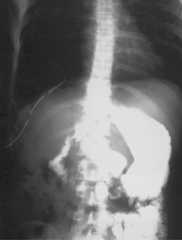

A thirty five year old male presented with breathlessness on routine exertion and symptoms of dyspepsia of a year duration. General physical examination was unremarkable, auscultation of the chest revealed presence of bowel sounds in the right side of the chest. Chest radiograph revealed a raised right hemidiaphragm, with its outlines not well discernible, mediastinal shift to the left and presence of air filled bowel loops in the right thoracic cavity (Fig 1). A provisional diagnosis of right sided diaphragmatic hernia was made and an upper gastrointestinal barium study was done which revealed presence of stomach, small intestine and parts of colon in the right thoracic cavity (Fig 2). A contrast enhanced CT scan of the thorax and abdomen was performed which confirmed presence of stomach, small intestine, large intestine and the right lobe of liver in the postero-lateral aspect of the thoracic cavity, discontinuity of the soft tissue line of the diaphragm with continuity of sub-diaphragmatic and supra-diaphragmatic densities through the defect suggestive of Bochdalek hernia (Fig 3). The right lobe of the liver was also hypoplastic. The patient was taken up for surgery and per operative findings revealed herniation of the stomach, coils of jejunum, ileum and colon through a smooth circular defect of 6cmx4cm size in the posterolateral aspect of the right hemidiphragm. The right lobe of the liver was hypoplastic and had herniated into the thoracic cavity. No hernial sac could be identified. The diaphragmatic defect was closed with polypropylene mesh and sutured in two layers with interrupted non-absorbable suture and the thoracic cavity was drained by a single chest tube. The patient had an uneventful postoperative recovery. A repeat upper GI barium study after 10 days of surgery revealed no evidence of any herniated bowel loop in the thoracic cavity (Fig 4).

Fig. 1.

Chest radiograph PA view showing raised right hemidiaphragm and presence of air filled bowel loops in the right thoracic cavity